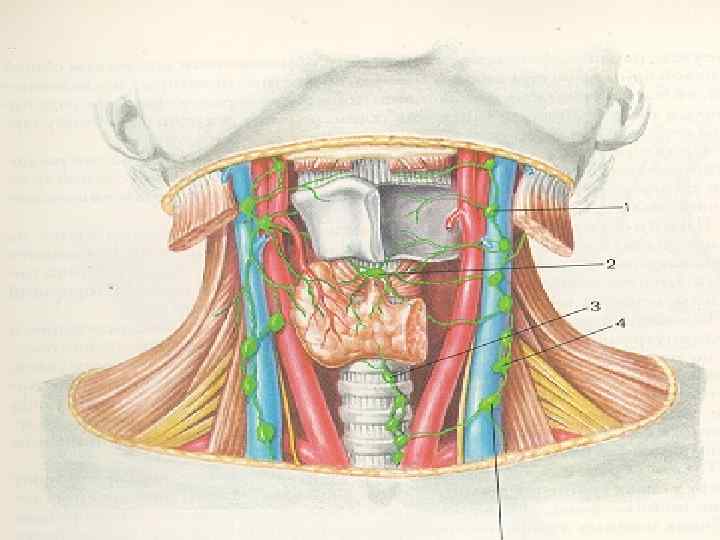

Методы исследования щитовидной железы 1 Клинико-физикальное обследование осмотр; ( деформация шеи, расширение вен шеи, одутловатость лица, пучеглазие) пальпация; (увеличение железы, выявление узлов) перкуссия; аускультация; измерение окружности шеи. II. Ларингоскопическое исследование III. Рентгенологическое исследование Пневмомедиастинум Пневмотиреография

Методы исследования щитовидной железы 1 Клинико-физикальное обследование осмотр; ( деформация шеи, расширение вен шеи, одутловатость лица, пучеглазие) пальпация; (увеличение железы, выявление узлов) перкуссия; аускультация; измерение окружности шеи. II. Ларингоскопическое исследование III. Рентгенологическое исследование Пневмомедиастинум Пневмотиреография